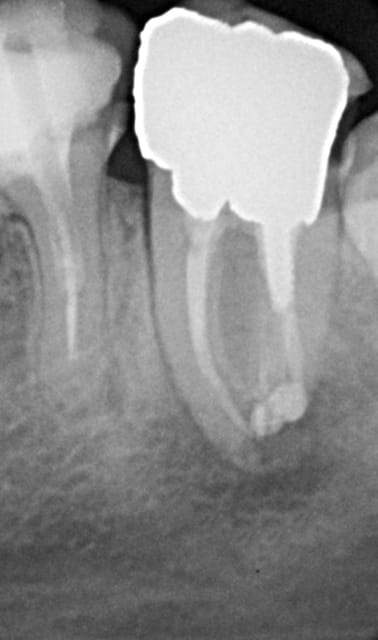

encore des radios,peut-etre assez moyen comme traitement...mais je vu pire...

les dernieres radios. patient en urgence ,abces... il voulait pas extraire la dent. j'ai lui bien explque et il a choisi de essayer de garder la dent. retrait,pas d'isolation avec la digue donc pas de tenon fibree,amalgam et screw post.traitement fait il ya 2 ans je crois.patient fidel de cabinet maintenent.

j'ai jamais utilise en roumanie l'amalgam et ca s'utilise pas du tout dans le cabinet du roumanie.